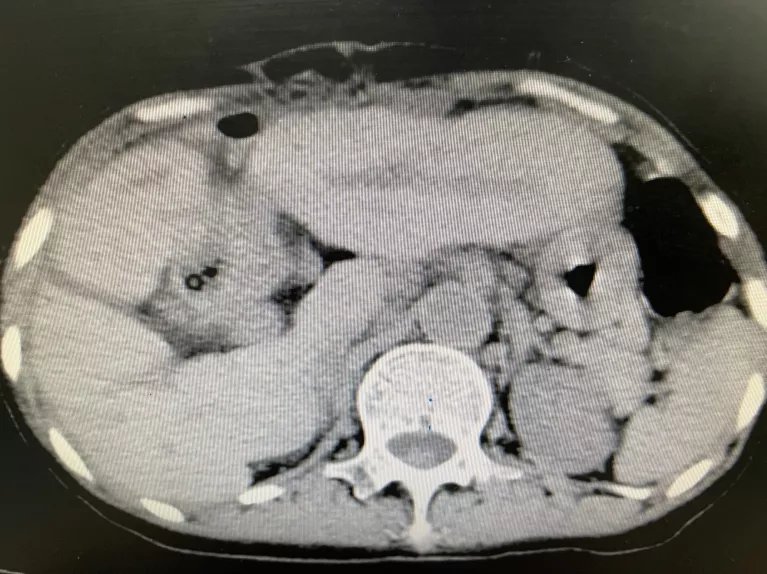

术后CT显示,结石清除干净。

“这个手术可以说将失血降至最低,用时最短,对患者打击最小,恢复最快”,术后,胆道外二科护士长胡霞红带领护理团队运用快速康复外科ERAS理念,采用术后多模式镇痛,早期鼓励患者开展机体功能锻炼等措施。术后第二天,患者即可进流食、下床活动;术后第三天复查CT显示:肝内胆管结石已全部取尽,于7月26日康复出院。